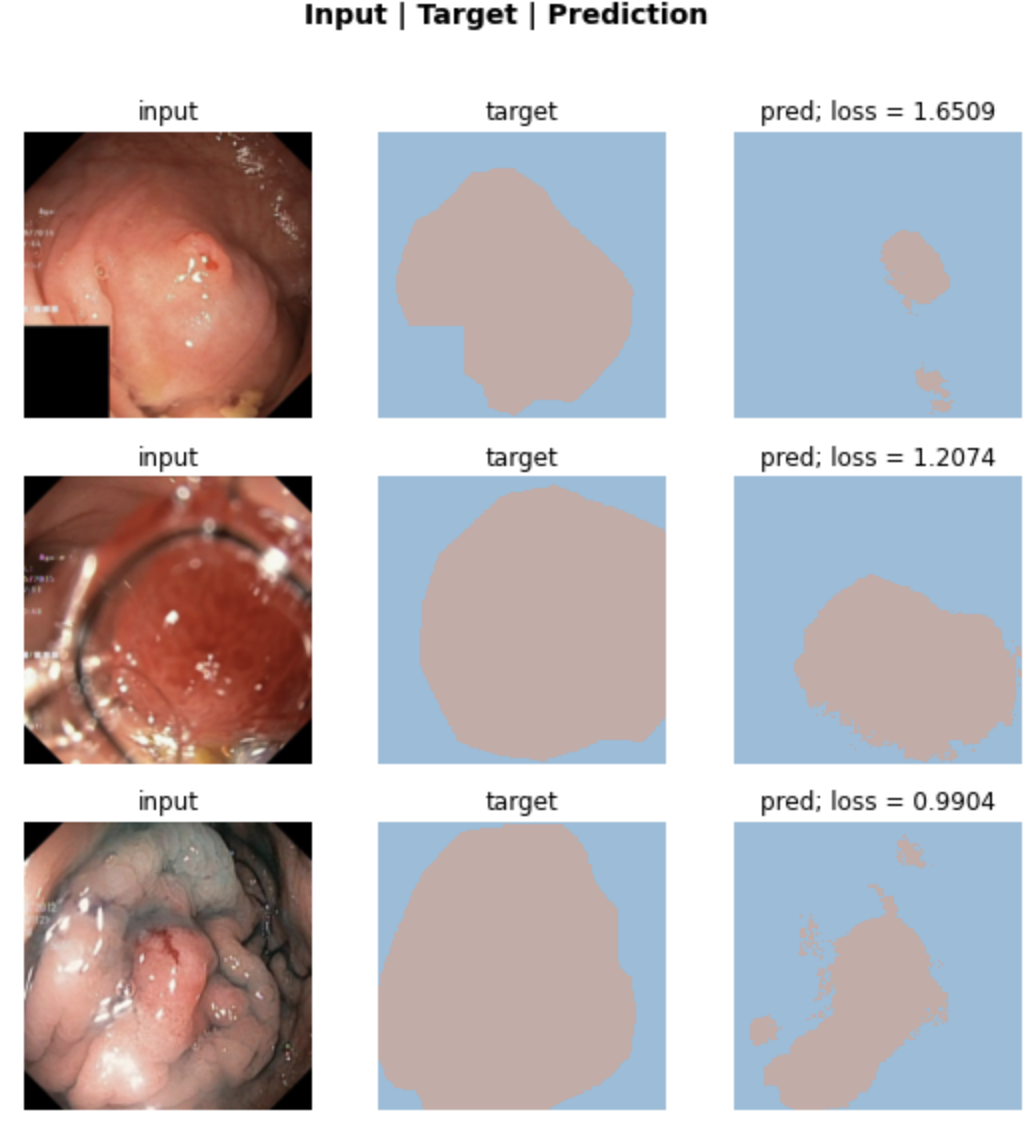

Results

Visualization of results

Target/Prediction